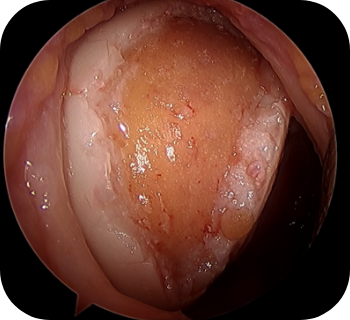

파열 범위가 큰 광범위 파열인 경우, 가능하면 일차 봉합술을 시행하는 것이 바람직하나, 내측으로 말려들어간 힘줄을 무리하게 당겨 봉합을 할 경우 재파열이 빈번하게 일어날 수 있습니다. 우선 관절경으로 견봉 성형 및 점액낭을 제거한 후 파열의 정도와 모양을 확인하고, 복원 불가능한 파열에서는 부분 복원술을 시행한 이후 피부조직이식술을 시행하게 되는데, 이는 노출된 상완 골두를 덮어주고 봉합한 힘줄을 보강시켜줄 수 있는 방법입니다.

▲ 회전근개 봉합술 전